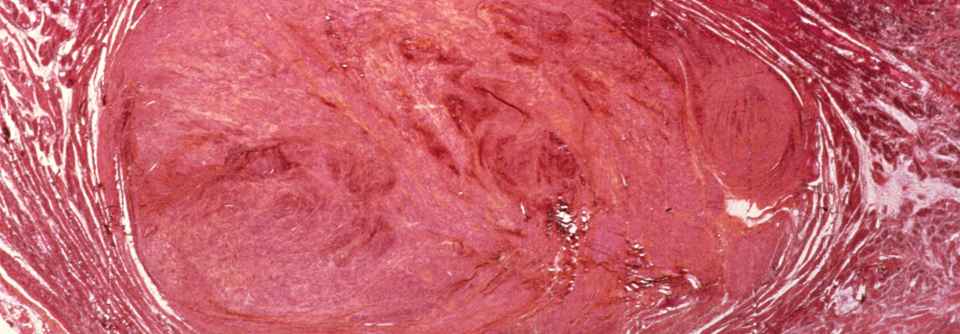

Endometriosezysten, wie hier im Ovar, können starke Schmerzen verursachen. Endometriosezysten, wie hier im Ovar, können starke Schmerzen verursachen. © Science Photo Library